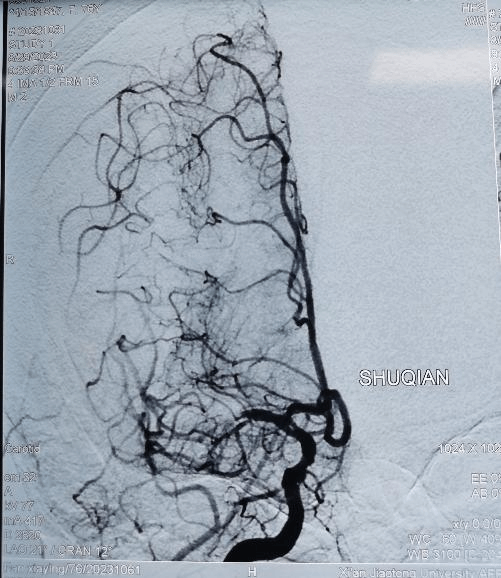

右侧大脑中动脉闭塞再通术前